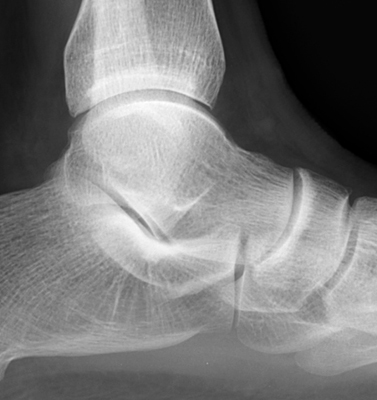

Diagnosis:Ankle effusion Discussion:One normal ankle radiograph (A), and one abnormal ankle radiograph (B) revealing a moderate effusion. The teardrop shaped density seen extending anteriorly from the ankle joint along the neck of the talus has been referred to as the "teardrop sign" of ankle effusion. This is a useful sign in the diagnosis of ankle joint effusion, and may alert the diagnostician to possible underlying pathology. References: